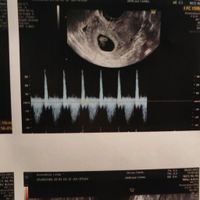

Ancora incredula apro questo post...mai risveglio poteva essere piΓΉ bello π spero che questo post si riempia di pancine π€°ππ